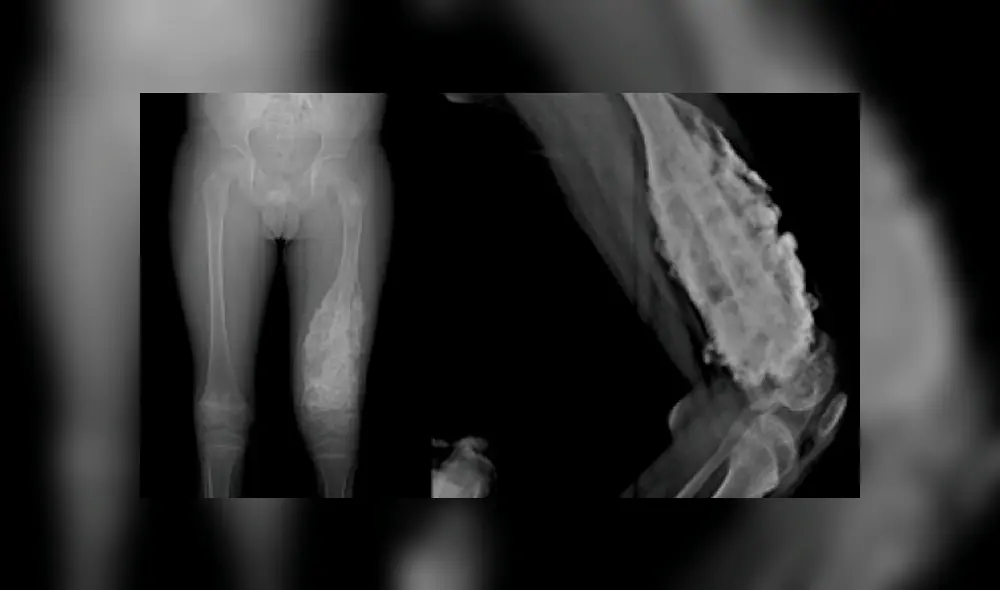

El osteosarcoma considerado como el cáncer óseo más común en niños es un tumor derivado de las células que generan el hueso, propiciando un crecimiento extremo de estos que produce dolor e hinchazón en las zonas afectadas.

Este tipo de enfermedad suele presentarse en los huesos más grandes del cuerpo como el brazo, muslo o espinilla, donde se desarrolla un crecimiento óseo más rápido. Sin embargo, su crecimiento se puede dar en cualquier otro hueso, extendiéndose luego al resto.

El osteosarcoma también conocido como el cáncer de huesos largos, por encontrarse generalmente en las extremidades de las piernas. Se le atribuye como consecuencia a un crecimiento muy rápido en adolescentes, presentándose mayormente en niños que en niñas.

El primer síntoma son el dolor e hinchazón en brazos y piernas, pudiendo empeorar con la realización de ejercicios físicos. Sin embargo, en ocasiones el bulto en el hueso comprometido puede presentarse varias semanas después de iniciado el dolor.

En algunos casos cuando el osteosarcoma ha afectado la pierna, el niño puede empezar a cojear, teniendo que percatarse de la presencia de fracturas que se dan por el debilitamiento del hueso.